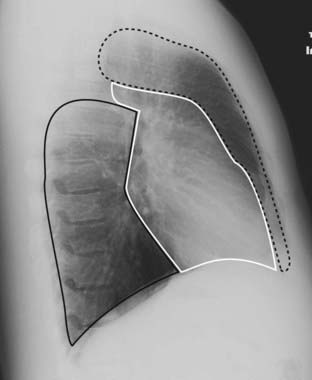

Figure 12-23 Emphysema.

On conventional radiographs, the imaging findings of COPD are hyperinflation, including flattening of the diaphragm, especially on the lateral exposure (solid white arrow in B), increase in the retrosternal clear space (dotted white arrow), hyperlucency of the lungs with fewer than normal vascular markings, and prominence of the pulmonary arteries secondary to pulmonary arterial hypertension (solid white arrows in A).